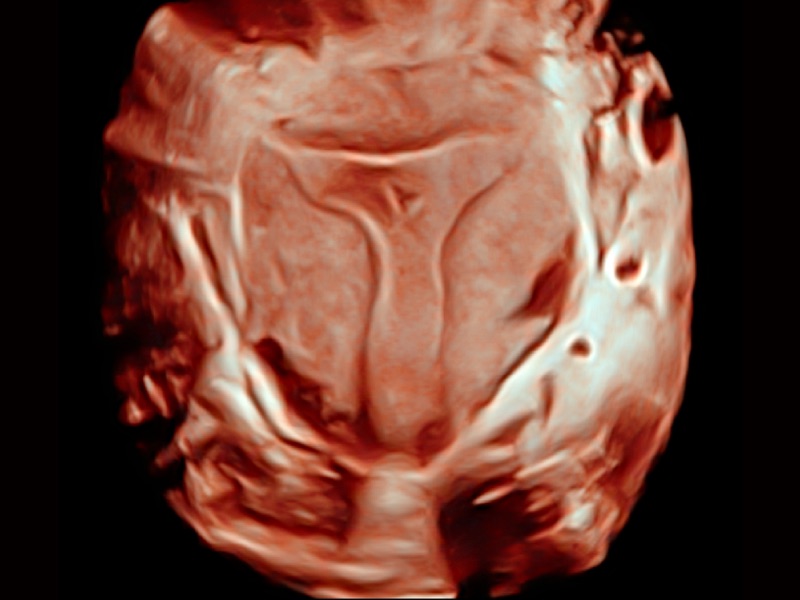

三維光影成像技術(shù)采用新型的渲染方式,增強(qiáng)邊緣信息,使得輪顯示清晰完整,為臨床提供豐富、直觀的三維結(jié)構(gòu),提供臨床診斷準(zhǔn)確性。

婦產(chǎn)科應(yīng)用